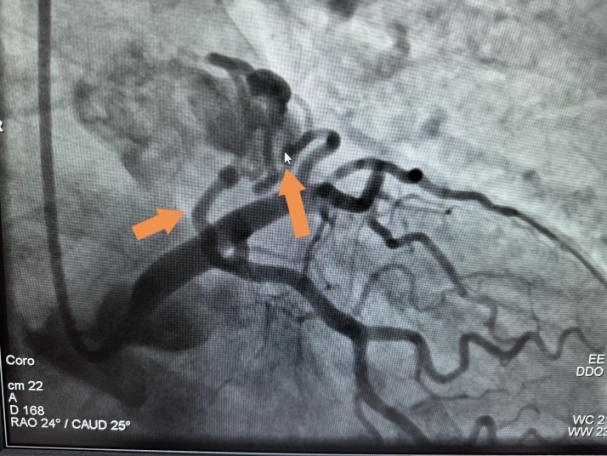

患者胸痛不适 不一定是冠脉本身狭窄 还有可能是心脏里的“小偷” 窃走了冠脉的血流 分流到了其他器官 77岁的徐阿姨 因反复胸痛不适半年 到奉贤区中心医院心血管内科就诊 据悉徐阿姨每次发作胸痛无明显原因 持续1~2分钟症状可自行消失 检查胸部CTA提示冠状动脉-肺动脉瘘 上面两张图片就是徐阿姨的检查影像,我们可以看到箭头所指的位置就是徐阿姨的左冠状动脉,发出两根瘘管。 冠状动脉瘘 冠状动脉瘘是冠状动脉的一种先天性或获得性异常,发生率在0.05%~0.9%。冠状动脉瘘形成会导致心肌缺血从而导致心绞痛发作,时间长了导致心脏扩大继而发作心衰。冠状动脉瘘自然闭锁的机会极少,且随着年龄增长会出现相应的并发症,故多主张早期治疗。 结合徐阿姨的症状及相关检查结果 医生建议内科介入治疗 经过术前充分评估 与徐阿姨及家属反复沟通后 手术团队选择介入下用弹簧圈对瘘管进行封堵 术中造影证实从左前降支发出双瘘至肺动脉 两处瘘管血管迂曲且流量大 手术持续1小时 经弹簧圈封堵术后两处瘘管分流消失 术后次日徐阿姨明显感觉胸痛症状消失 这也是奉贤区首例冠状动脉瘘封堵术 左(术前):由左前降支发出2根瘘管至肺动脉形成瘘。 右(术后):用弹簧圈对瘘管进行封堵术后,瘘消失。 冠状动脉瘘封堵术 具有创伤小、时间短、费用少等优点。在不增加患者痛苦及操作风险的同时,为患者进行精准治疗。 奉贤区中心医院心血管内科 科室为奉贤区首批医学重点学科、奉贤区胸痛诊治中心,奉贤区房颤中心并取得国家胸痛及房颤中心认证。目前开放床位85张(CCU20张,A类病房5张)。共有医护人员64人(博士5名、硕士10名、博士生导师1名、硕士生导师3名),其中主任医师3人、副主任医师5人、主治医师10人。年门急诊业务量12万人次,年出院人次近4200余人次,介入诊疗2600余人次。亚学科建设成熟,有冠脉介入组、起搏组、电生理组、高血压心衰组。